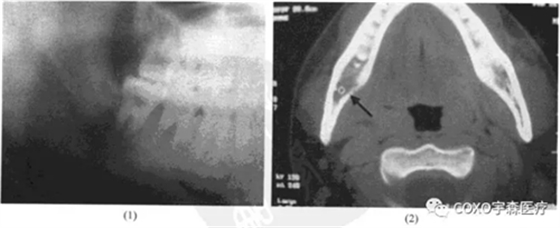

檢查:7] II度松動(dòng),81] III度松動(dòng),右頜下扣及1cm×1cm,質(zhì)地較軟,有壓痛之腫塊。X線片示:8]根尖區(qū)陰影;CT示:8]區(qū)骨髓腔稀疏,舌側(cè)骨板有蟲(chóng)蝕樣破壞(圖13-12).

患者因牙痛,夜間加劇,下唇麻木和局部出現(xiàn)腫塊而就診。X線攝片顯示:8]根尖陰影,因而首先考慮為根尖周病,但因有下唇麻木及腫塊存在又應(yīng)考慮頜骨中心性病損,特別是惡性腫瘤。再追問(wèn)病史有白血病史,又不排除根尖周病的可能。為進(jìn)一步證實(shí)其病損的性質(zhì),拔牙后病理證實(shí)為白血病侵犯。